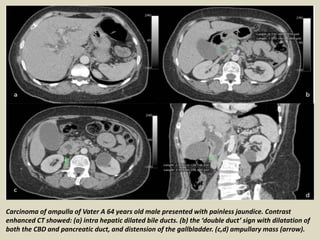

Carcinoma of ampulla of Vater A 64 years old male presented with painless jaundice. Contrast

enhanced CT showed: (a) intra hepatic dilated bile ducts. (b) the ‘double duct’ sign with dilatation of

both the CBD and pancreatic duct, and distension of the gallbladder. (c,d) ampullary mass (arrow).

Carcinoma of ampulla of Vater MRI (e) CoronalT1-FS-Gado, (f) CoronalT2, and (g) MRCP)

showed intrahepatic and common bile ducts dilatation with abrupt distal termination